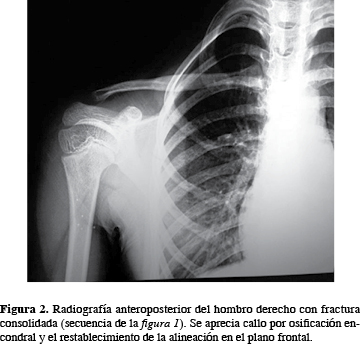

Fractura de tercio medio tipo 2.